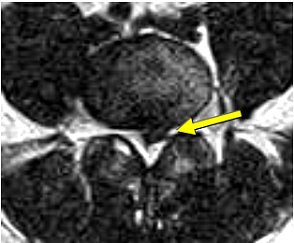

![]() |

| Above, preaxial loaded. Below, axial-loaded image. Central subligamentous disk herniation and discogenic disease at L5-S1 impressing the thecal sac only after axial loading is applied. L4-L5 bulging, discogenic disease, and a central subligamentous disk herniation impressing on the thecal sac. Bulging and discogenic disease at all other levels. |